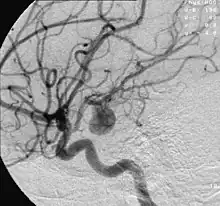

Anevrismul reprezintă o formațiune vasculară cu aspect tumoral, localizată pe traiectul unei artere (cel mai des) sau vene[1]. Se prezintă ca o dilatare (ca un sac) a vasului sanguin și poate fi localizat oriunde în organism[2]. Cu toate acestea, cel mai adesea el se dezvoltă în segmentul abdominal al arterei aortice și la nivelul vaselor creierului (anevrism cerebral)[3]. În majoritatea cazurilor este asimptomatic.

- Clinicile moderne pentru tratamentul unor astfel de patologii se aplică chirurgiei endovasculare utilizând embolia iatrogenică cu materiale sintetice din segmentul arterei anormale, sau impunerea unui clip pe gâtul anevrismului pentru a opri zona din sânge.